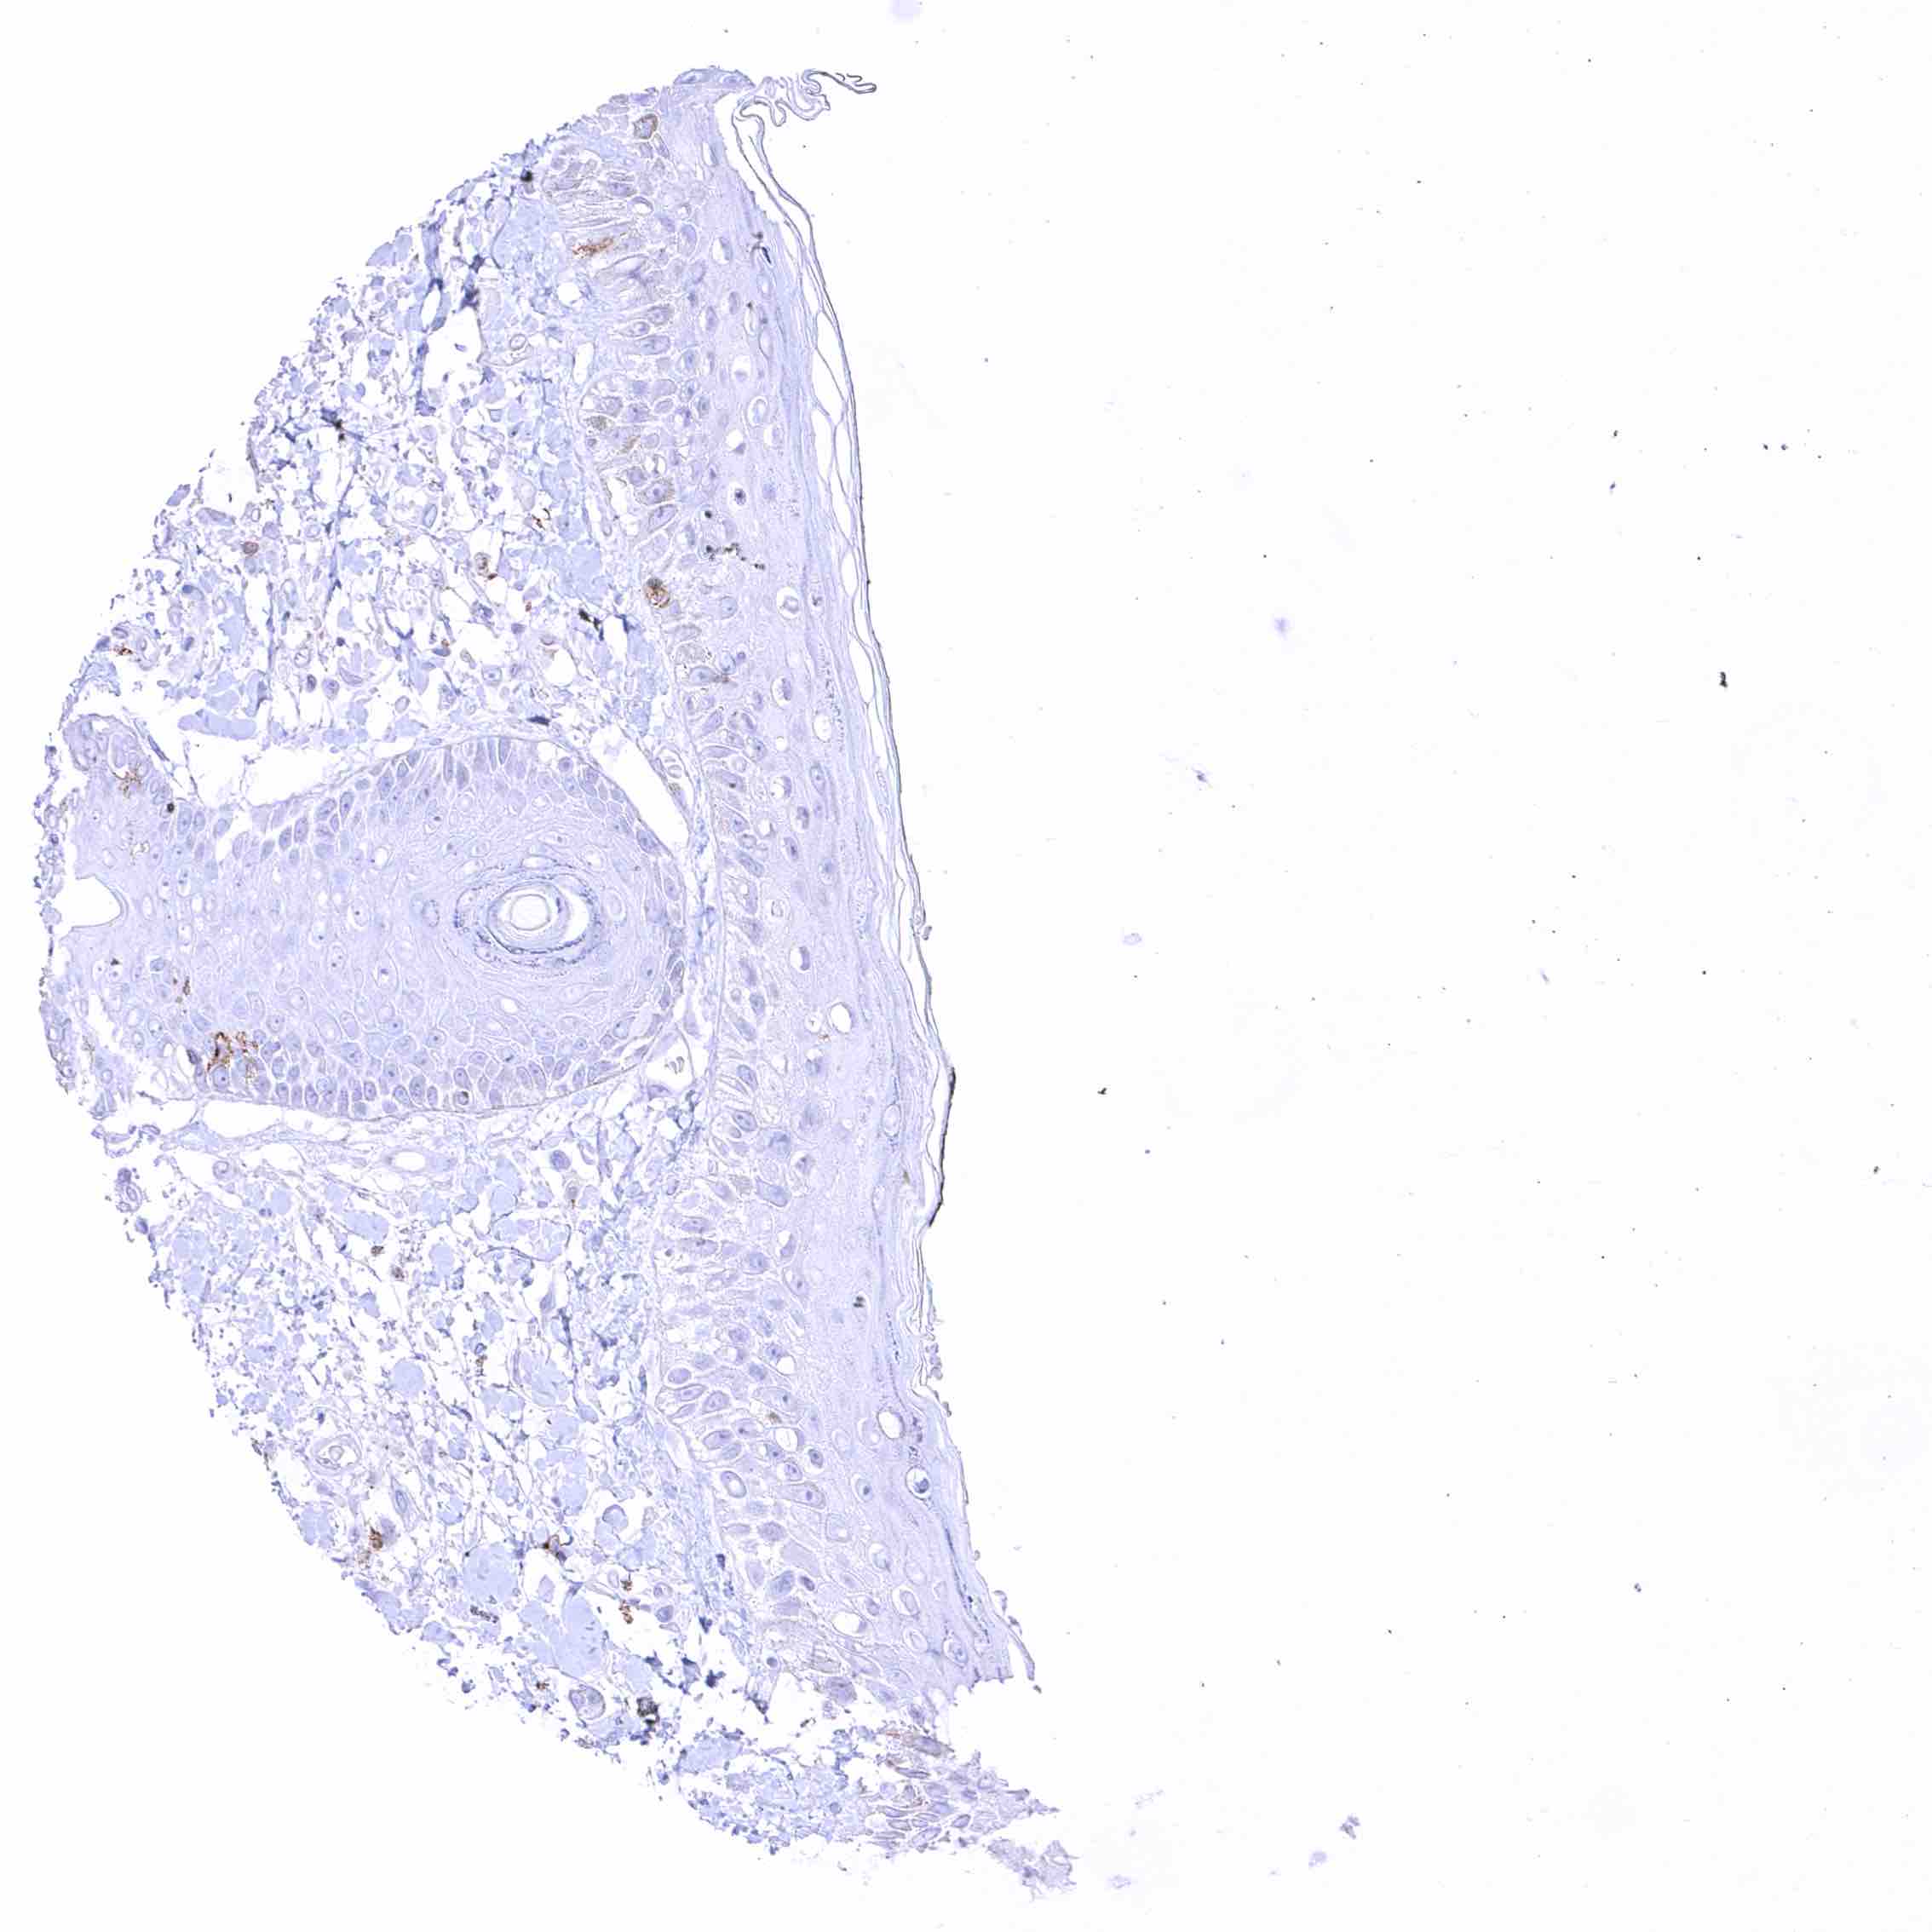

Positive control = Appendix: A distinct membranous CD70 staining should be seen in a subset of inflammatory cells (especially interfollicular).

Negative control = Appendix: CD70 staining should be absent in epithelial cells.

| Appendix | Distinct CD70 positivity of a fraction of lymphocytic cells, predominantly interfollicular. Epithelial cells are CD70 negative. | |

| Tonsil | Membranous CD70 staining of variable intensity in subsets of inflammatory cells (mostly lymphocytes). Most CD70 positive cells are interfollicular. Squamous epithelium remains CD70 negative. | |